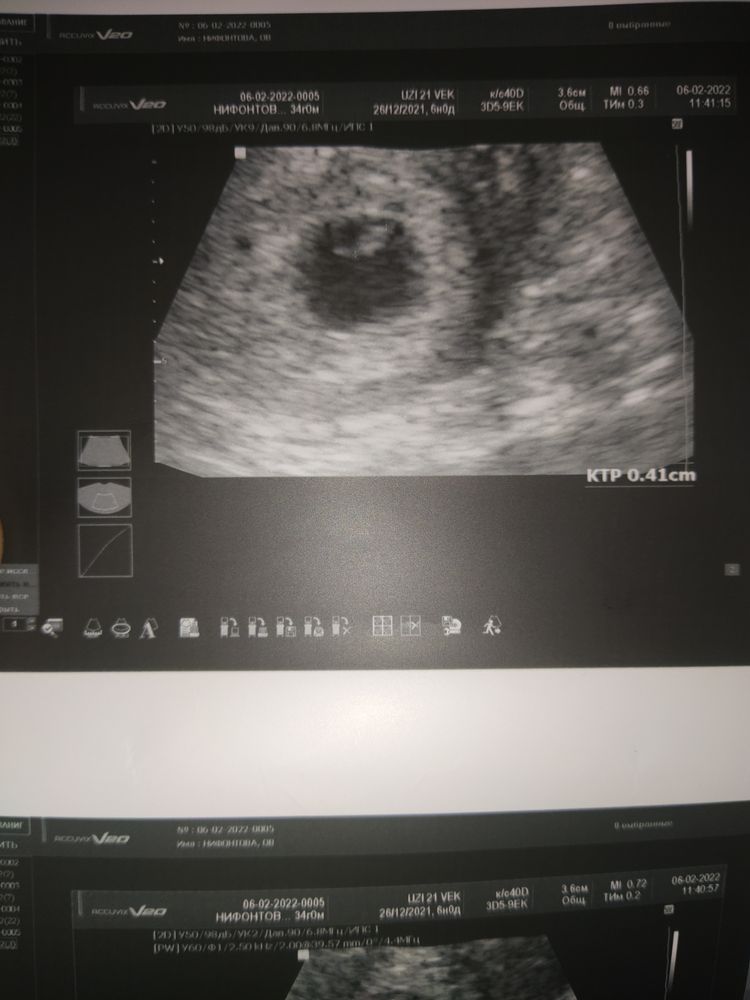

Узи первого триместра форум

Узи первого триместра форум 117 фото